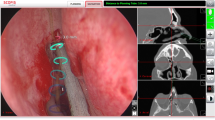

Recently, there has been an expansion of novel technologies in simulation training. The aim of this review was to examine existing evidence about training simulators in rhinology, their incorporation into real training programmes and translation of these skills into the operating room. The first part focuses on the virtual and augmented reality simulators. The second part describes the role of physical (i.e. non-computer-based) models of endoscopic sinus surgery.

In the previous chapter, we have described virtual reality (VR) and augmented reality (AR) simulators of endoscopic sinus surgery (ESS). An ideal model for a training or fellowship programme would score highly in all standard measures of validity whilst maintaining an attainable cost. This is a challenging goal that is worthy of pursuit given that simulation training has been shown to be cost-effective option in other domains [1]. Non-AR or VR models are attractive ways to fill gaps in simulation training whilst reducing costs given the overheads associated with computer-based models [1].

In this chapter, physical (i.e. non-computer based) models of ESS will be evaluated in order to clarify their utility in training ENT surgeons.